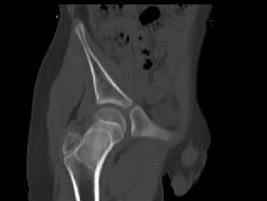

问题 男,13岁,右髋部疼痛不适,无红肿,请结合所提供的图像,选择最佳答案 ( )

选项 A、内生软骨瘤 B、骨纤维结构不良 C、骨巨细胞瘤 D、畸形性骨炎 E、非骨化性纤维瘤

答案 B